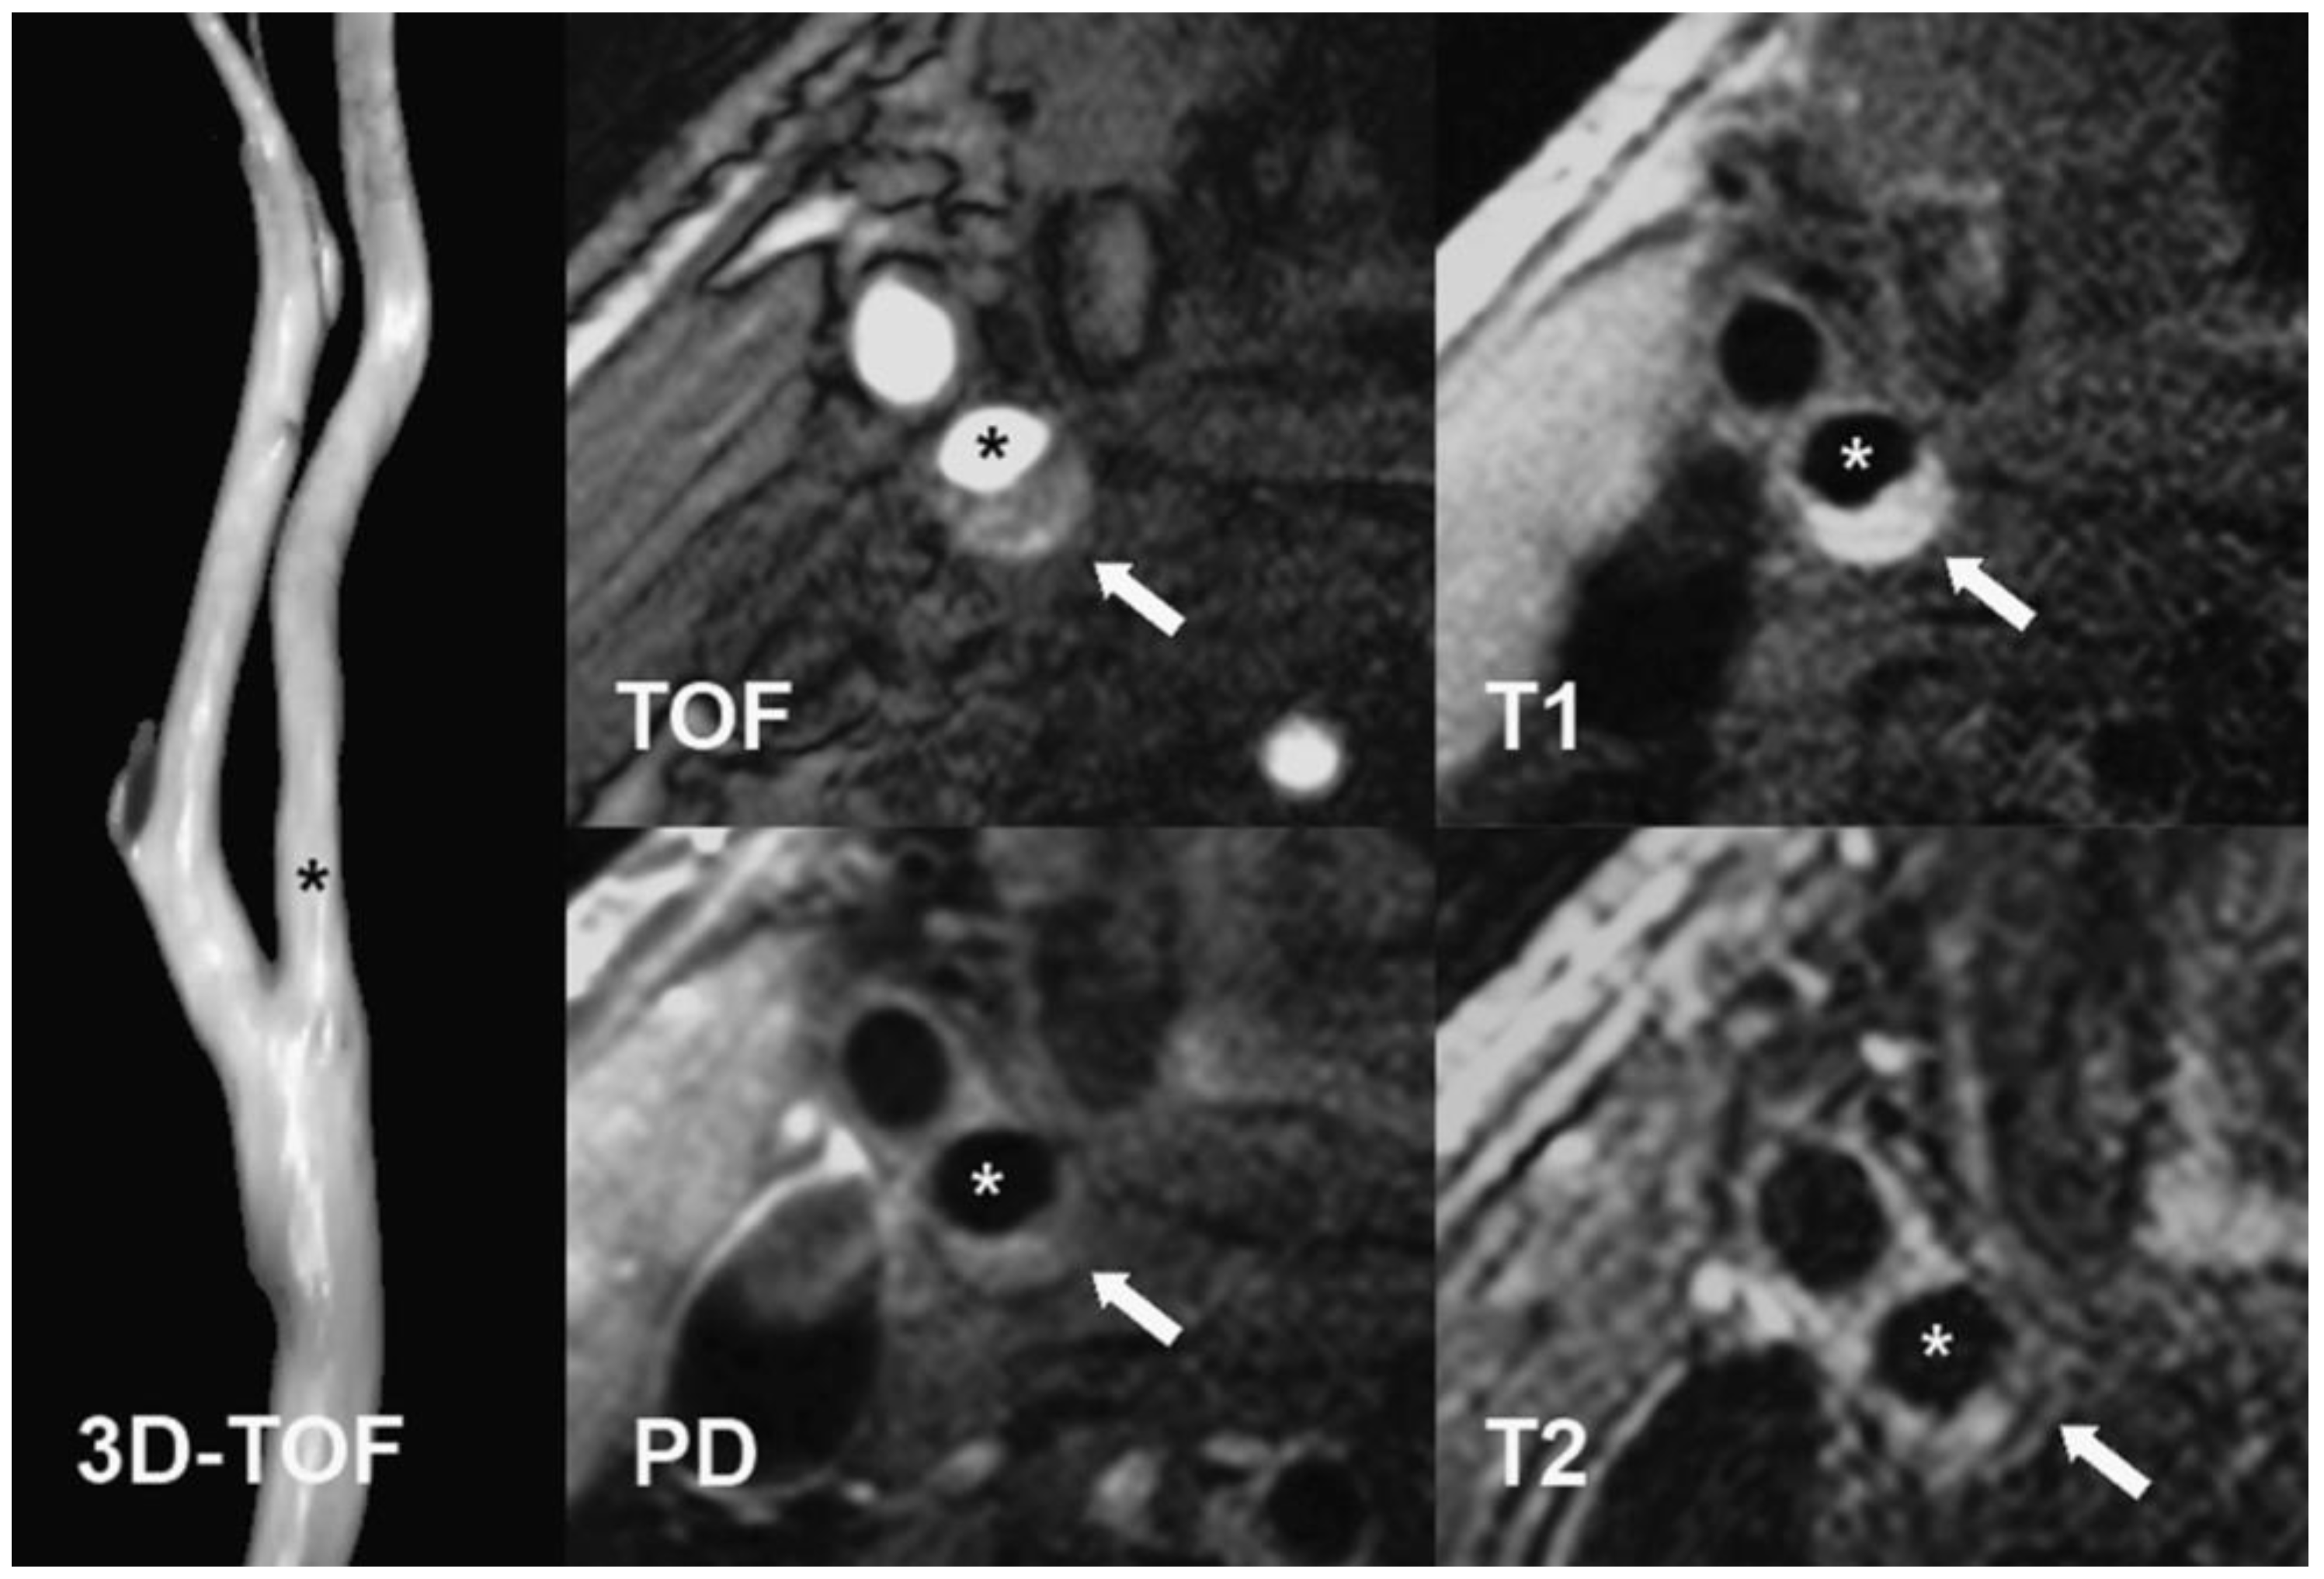

4.2. Arteriosclerotic Plaque Examination

4.3. MRI Protocol

- Cai, J.M.; Hatsukami, T.S.; Ferguson, M.S.; Small, R.; Polissar, N.L.; Yuan, C. Classification of human carotid atherosclerotic lesions with in vivo multicontrast magnetic resonance imaging. Circulation 2002, 106, 1368–1373. [Google Scholar] [CrossRef]